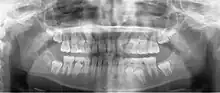

Panoramic radiograph showing horizontally impacted lower wisdom teeth.